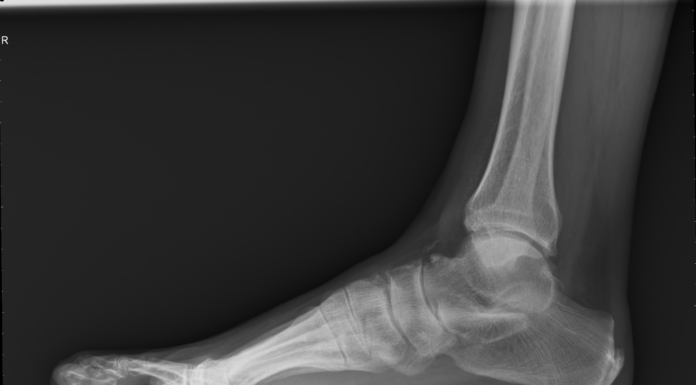

RUBRICA - Tendinite del tibiale: termine colloquiale per definire la tendinopatia o la disfunzione del tendine tibiale posteriore.

Il compito principale del tendine tibiale posteriore è l’inversione della caviglia e la flessione plantare del piede. E’ fondamentale nel cammino,...